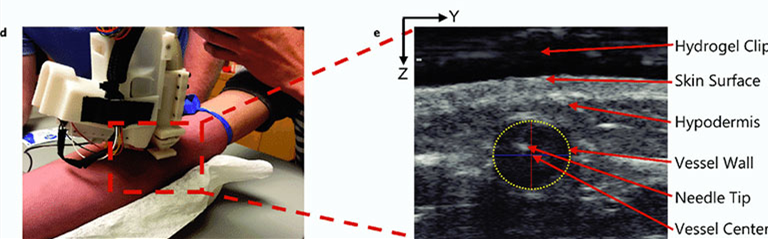

临床医生会进行以下设置:将机器置于对象的手臂进行定位,对目标区域进行消毒/擦拭,应用超声水凝胶并选择目标静脉的中心(如图所示)。然后,设备使用这些坐标来确定必要的运动学,以确保针尖在血管中心与超声成像平面相交。

(d)在研究过程中将器械放置在前臂上方。(e)超声图像显示成功静脉穿刺后目标血管中存在的针尖。血管壁由黄色虚线椭圆标识。图像中的Z轴表示容器深度,Y轴表示容器的矢状位。相对于超声换能器头(图像顶部)记录血管和针尖的位置。

一旦对准并稳定,操作员便开始操作程序,然后注射轴滑架将连接的针尖置于参与者的前臂以25度角向前驱动到静脉中心的目标,插入针头并抽出5毫升血液样本。